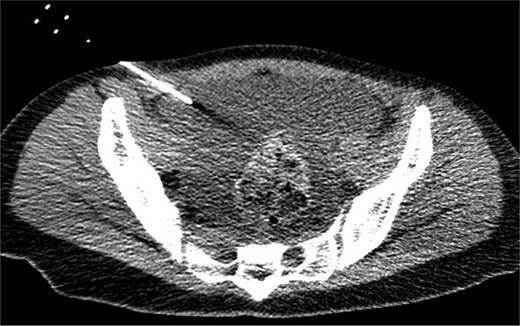

On the fifth day, the ascitic fluid increased in volume, and an open distal pancreatectomy was considered. However, her condition was stable. CT-guided abdominal drainage was performed, and a 10 Fr drainage tube was inserted for peritoneal lavage (Fig. 4). EUS-guided transgastric drainage of the pseudocyst in the omental bursa was performed. The pseudocyst was punctured; a balloon was dilated through the posterior wall of the stomach (Fig. 5a–c), and three tube stents of 7 Fr were implanted (Fig. 5d). The Amy and P-Amy levels in ascites were 9429 and 8877 IU/L, respectively; then, peritoneal lavage was performed daily. On the 12th day, contrast-enhanced CT revealed reduced pseudocyst size (Fig. 6). The patient was discharged on the 16th day (Fig. 7). Three years later, the patient is living her daily life without any complications.

CT of the pelvic region on the fourth day. An increase in ascitic fluid was observed. CT-guided abdominal drainage was performed, and a 10 Fr drainage tube was placed.